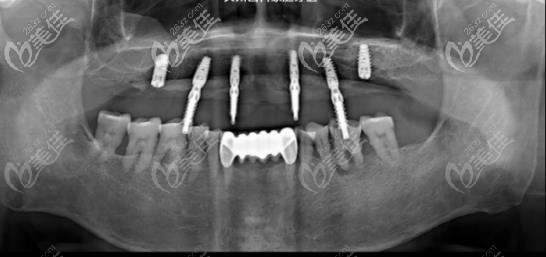

術(shù)前,這位叔叔上半口牙齒近乎全部脫落,就剩下幾顆牙齒,但是并不能用于吃飯的咬合,聽這位叔叔說“也戴過假牙,但是磨嘴、總掉、咬不成東西”等等,問題還是比較困擾。

在家人的陪伴下來到了曲江大川口腔,到院后表示就想能正常吃個(gè)飯,院內(nèi)醫(yī)生在經(jīng)過檢查后定出方案:拔除剩余三顆殘冠,進(jìn)行半口種植修復(fù),通過植入6顆植體,再帶上連橋冠修復(fù)。

叔叔的手術(shù)時(shí)間一共進(jìn)行了一個(gè)半小時(shí),當(dāng)術(shù)后為叔叔戴上臨時(shí)牙冠的時(shí)候,叔叔表示“多少年沒體會(huì)過嘴里有牙的感覺了,以后終于可以想吃什么就吃什么了”